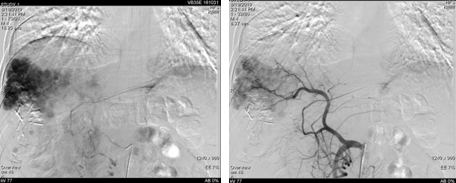

遂继续以碘油4 ml+0.9%氯化钠20 ml+吡柔比星20 mg+雷替曲塞2支方案,行第二次TACE治疗。

图片

图:第二次TACE治疗

为进一步抑制肿瘤进展,经多学科团队(MDT)讨论,予患者我国自主研发的抗血管生成药物联合PD-1单抗进行治疗。2019年8月19日复查,肝增强CT示,肝右叶占位性病变介入术后改变,其内异常强化,考虑肿瘤存活或复发,考虑肝右叶后段原发性肝癌。再次行TACE治疗。